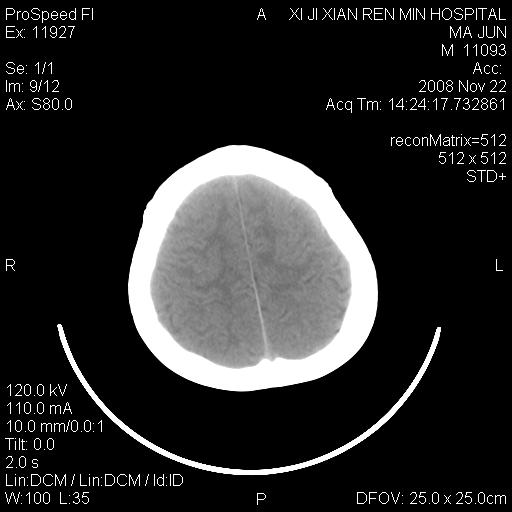

双侧侧脑室前角,三角区旁及半卵圆中心区白质呈低密度改变,半卵圆中心区病灶呈片状融合趋势,无软化征像,脑室无扩张,各神经核团无异常改变,脑皮质无萎缩等征像,结合病史考虑髓鞘发育不良性脑白质病,异染性脑白质营养不良可能性大.不除外多发性硬化等其他改变,建议磁共振检查

脑白质减少,双侧侧脑室额角旁及半卵圆中心可见对称性略低密度影,边缘尚清,考虑脑白质发育不良